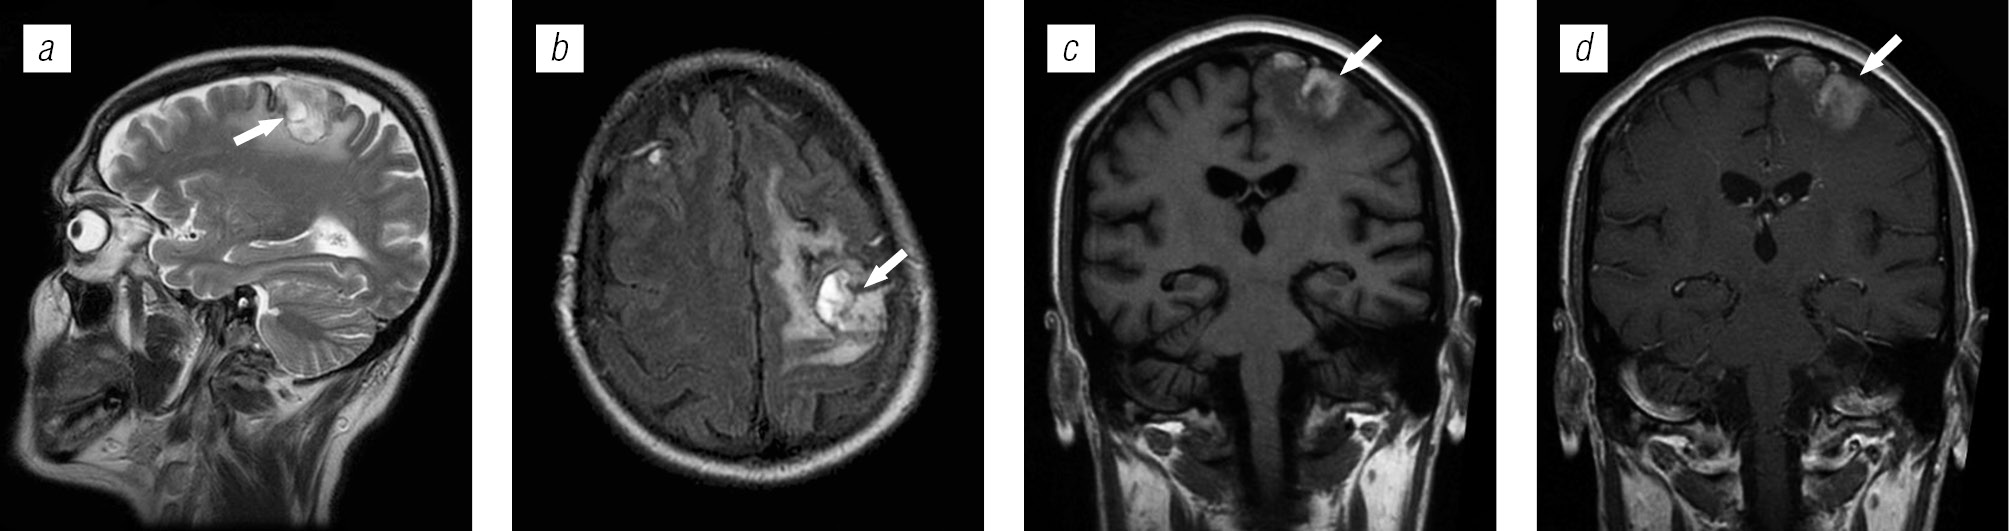

Структура оппортунистических и вторичных заболеваний была представлена токсоплазмозом головного мозга (18,3 %), герпесвирусными поражениями (12,2 %), прогрессирующей мультифокальной лейкоэнцефалопатией (10,24 %), нейроинфекцией неуточненной этиологии (12,2 %), криптококкозом (4,39 %), туберкулезом (2,44 %), лимфомой головного мозга (2,44 %), МАК-инфекцией (0,24 %).